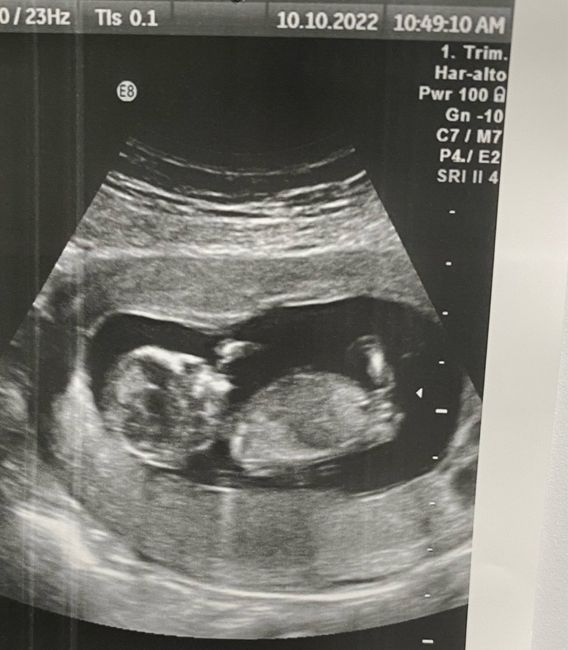

Buongiorno mamme! Ieri ho fatto la traslucenza nucale, mi hanno detto che dovrò fare anche il dna fetale perché l’esame del sangue ha riportato un rischio per trisomia 21 di 1:600 che è sempre basso ma con le nuove direttive sanitarie, vogliono che...